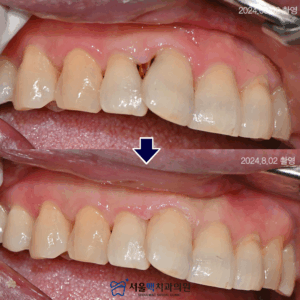

“앞니 치아사이에 검은 것이 보여요!

어떻게 치료해야 하나요?”

라는 이유로 내원하신 분의

사례를 소개해드리겠습니다.

처음 내원하셨을 때의 모습입니다.

환자분께서 말씀하신 검은 점은

‘치아 우식’으로 인접면에 발생하여

상당히 진행된 모습을 보이셨는데요.

화살표를 보시면 인접면 우식이

치아뿌리쪽으로 진행되어

잇몸이 내려간 부위에 더욱 음식물이 잘 끼고,

통증 및 불편감을 느끼셨으리라 생각됩니다.

방사선촬영을 통해

우식의 진행을 확인한 후 제거하였는데요.

다행히 신경이 있는

치수까지 진행되지 않아서 우식만 제거하고,

자연치아색과 매우 유사며

강도도 좋은 ‘복합레진’으로 충전해드렸는데요.

앞서 말씀드린대로,

인접면 우식은 충치 부분을

제거하기 위한

접근이 까다롭고 치아형태를 살리는 것은

온전한 의료진의 실력이라고 할 수 있습니다.

환자분의 치열이 약간 겹쳐져 있어

더욱 섬세한 치료가 필요했는데요.

접근하기 어려운 잇몸방향까지 꼼꼼하게 제거하고,

앞니인 만큼 더욱 색상과

형태를 자연스럽게 충천해드렸습니다.